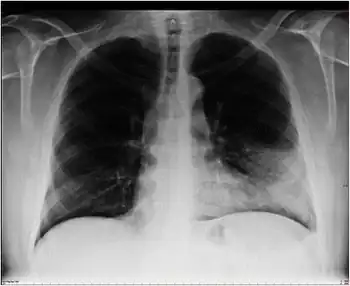

| Atypical pneumonia- X-Ray chest showing right peribronchial central infiltrate | |

Chest radiographs (X-ray photographs) often show a pulmonary infection before physical signs of atypical pneumonia are observable at all.[5] This is occult pneumonia. In general, occult pneumonia is rather often present in patients with pneumonia and can also be caused by Streptococcus pneumoniae, as the decrease of occult pneumonia after vaccination of children with a pneumococcal vaccine suggests.[16][17]

Infiltration commonly begins in the perihilar region (where the bronchus begins) and spreads in a wedge- or fan-shaped fashion toward the periphery of the lung field. The process most often involves the lower lobe, but may affect any lobe or combination of lobes.[5]